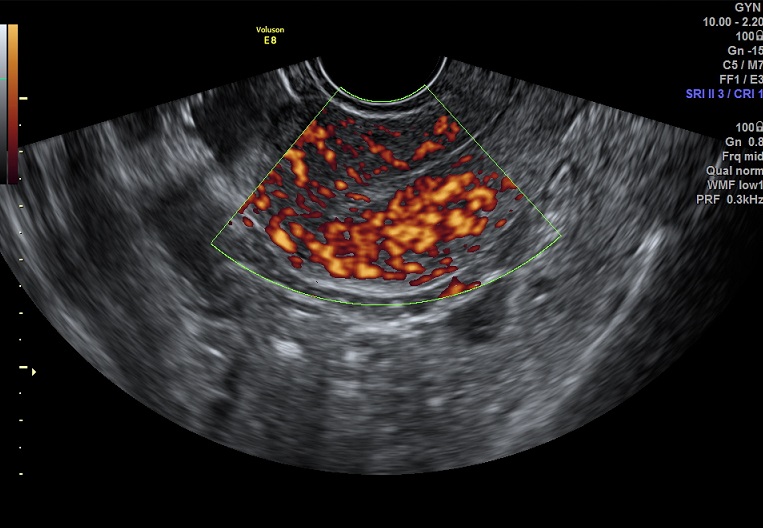

| 女性,25岁,继发性不孕1年余,难免流产4次。 | ||

2015-3-23 月经第19天检查 |

2015-3-23图示